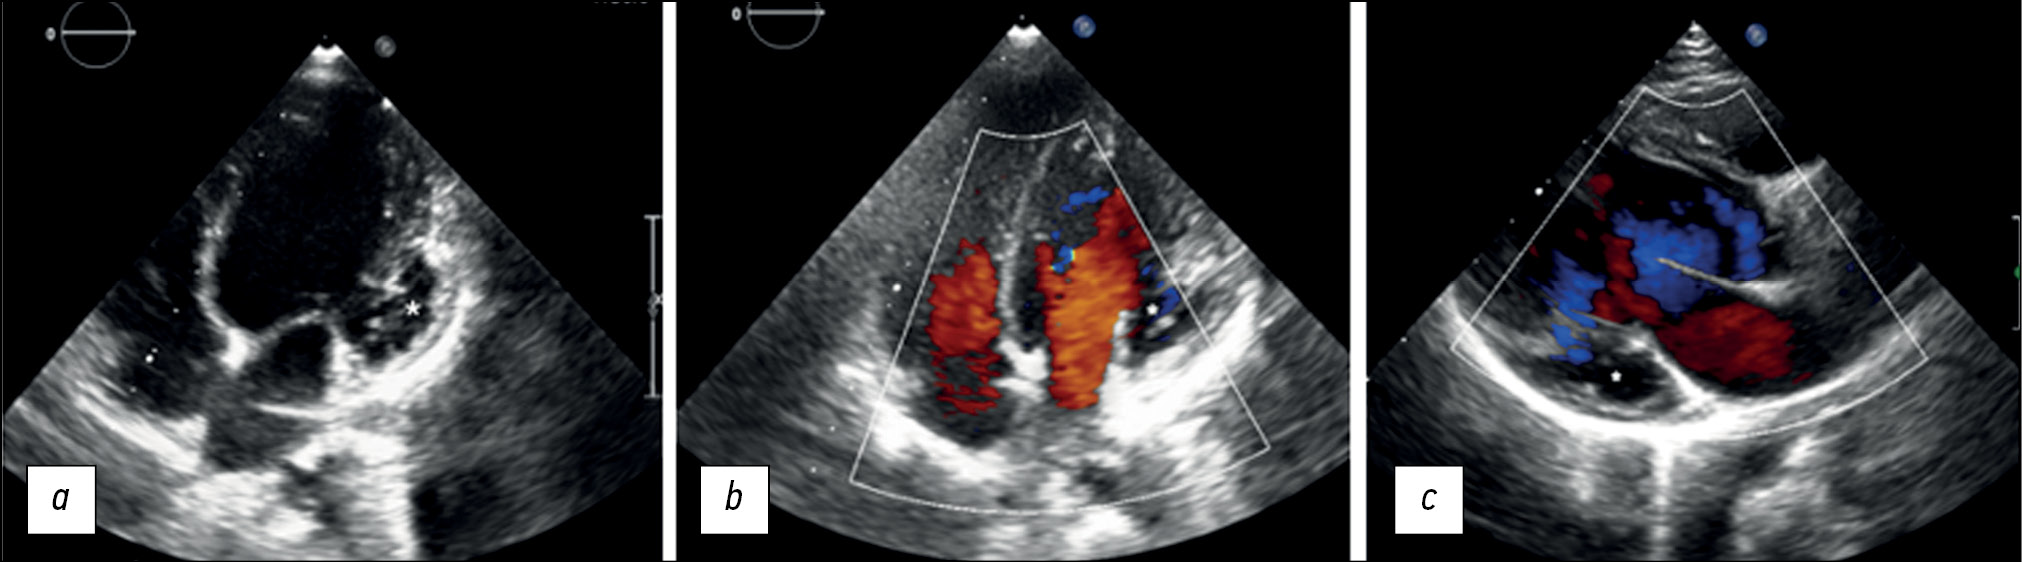

Left ventricular noncompaction with ventricular aneurysm in a 6-year-old patient

Ventricular noncompaction is a rare type of cardiomyopathy often associated with a ventricular aneurysm. We present a clinical case of a 6-year-old female who arrived at our clinic complaining of physical exertion. Echocardiography revealed prominent trabeculations in the left ventricular wall and a lateral-basal part bulging out, indicating noncompaction of the left ventricular myocardium with an aneurysm. With a noncompacted-to-compacted myocardium ratio of 2.6, magnetic resonance imaging revealed the presence of noncompacted myocardium. It also revealed impaired left ventricular systolic function and a left ventricular aneurysm with myocardial scarring. Coronary angiography ruled out coronary artery disease. Therefore, myocardial scarring was caused by noncompacted myocardium microcirculatory disorder.